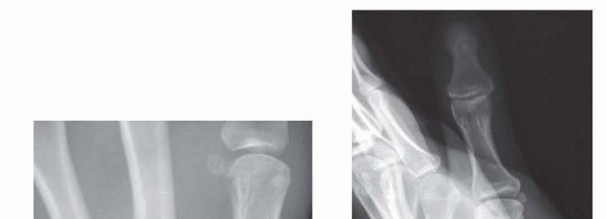

Clinical & Radiographic Imaging Archive

Clinical Image